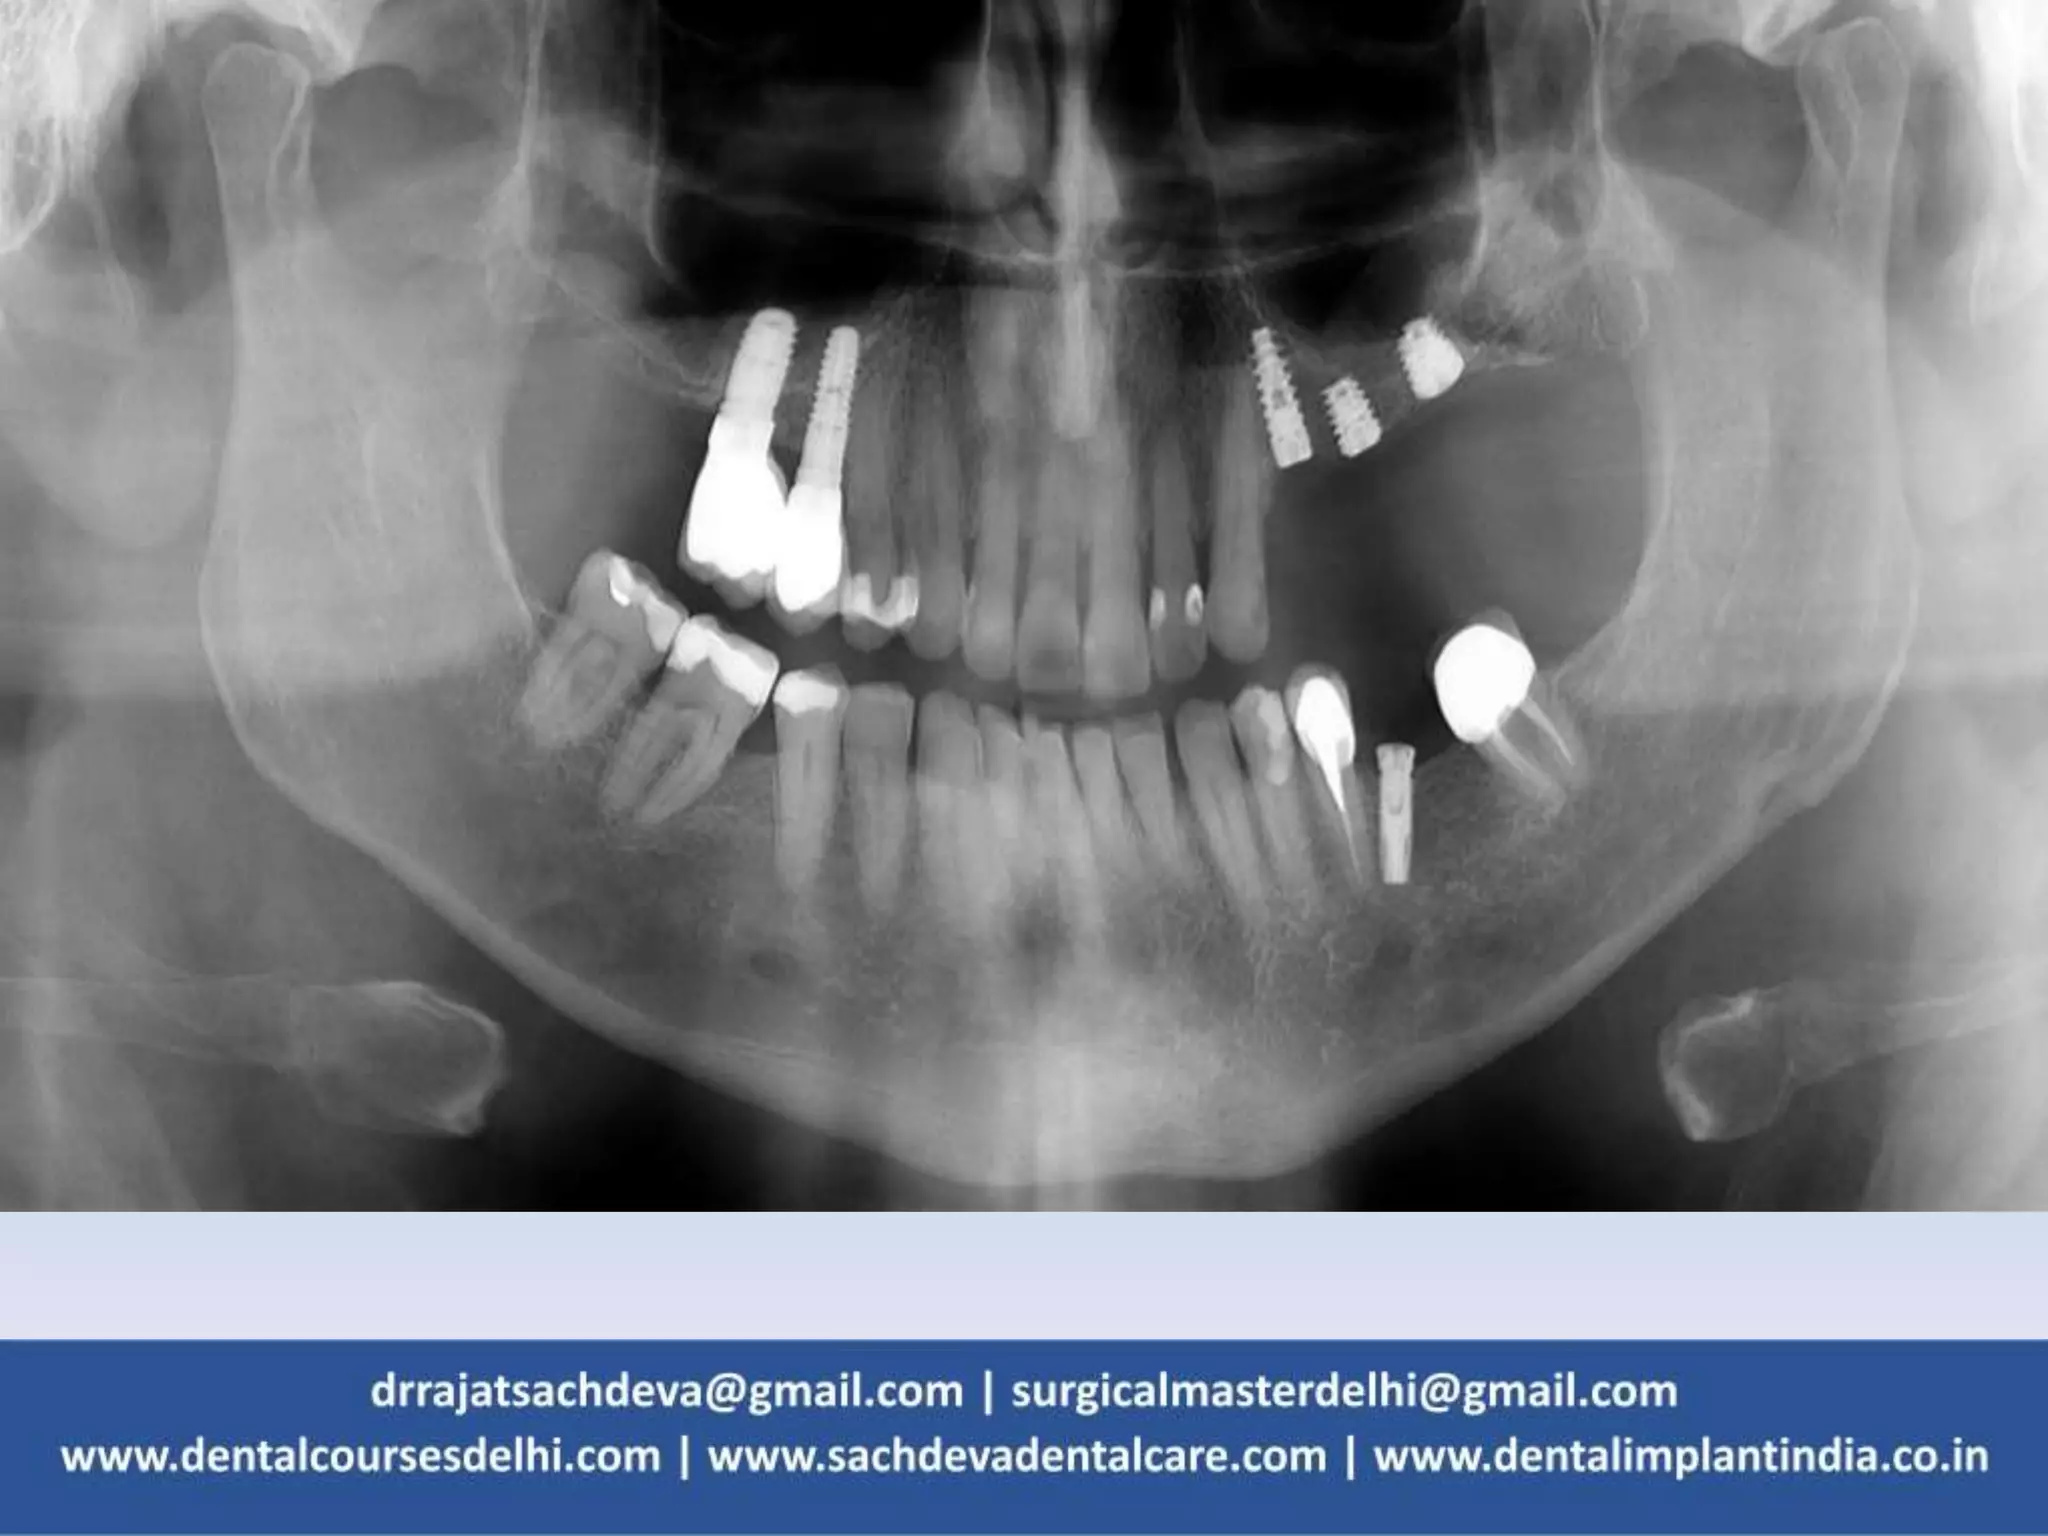

MANDIBULAR ANTERIOR OSTEOTOMY SITE

FRACTURE OF BONE

– Although it is more common in atrophic

mandibles as they are associated with

diminished blood supply.

– May occur during implant insertion or during

tightening of implants when adequate

mandibular support is not provided.

– Radiological examination should be thoroughly

evaluated for height and labial-lingual width of

mandible.